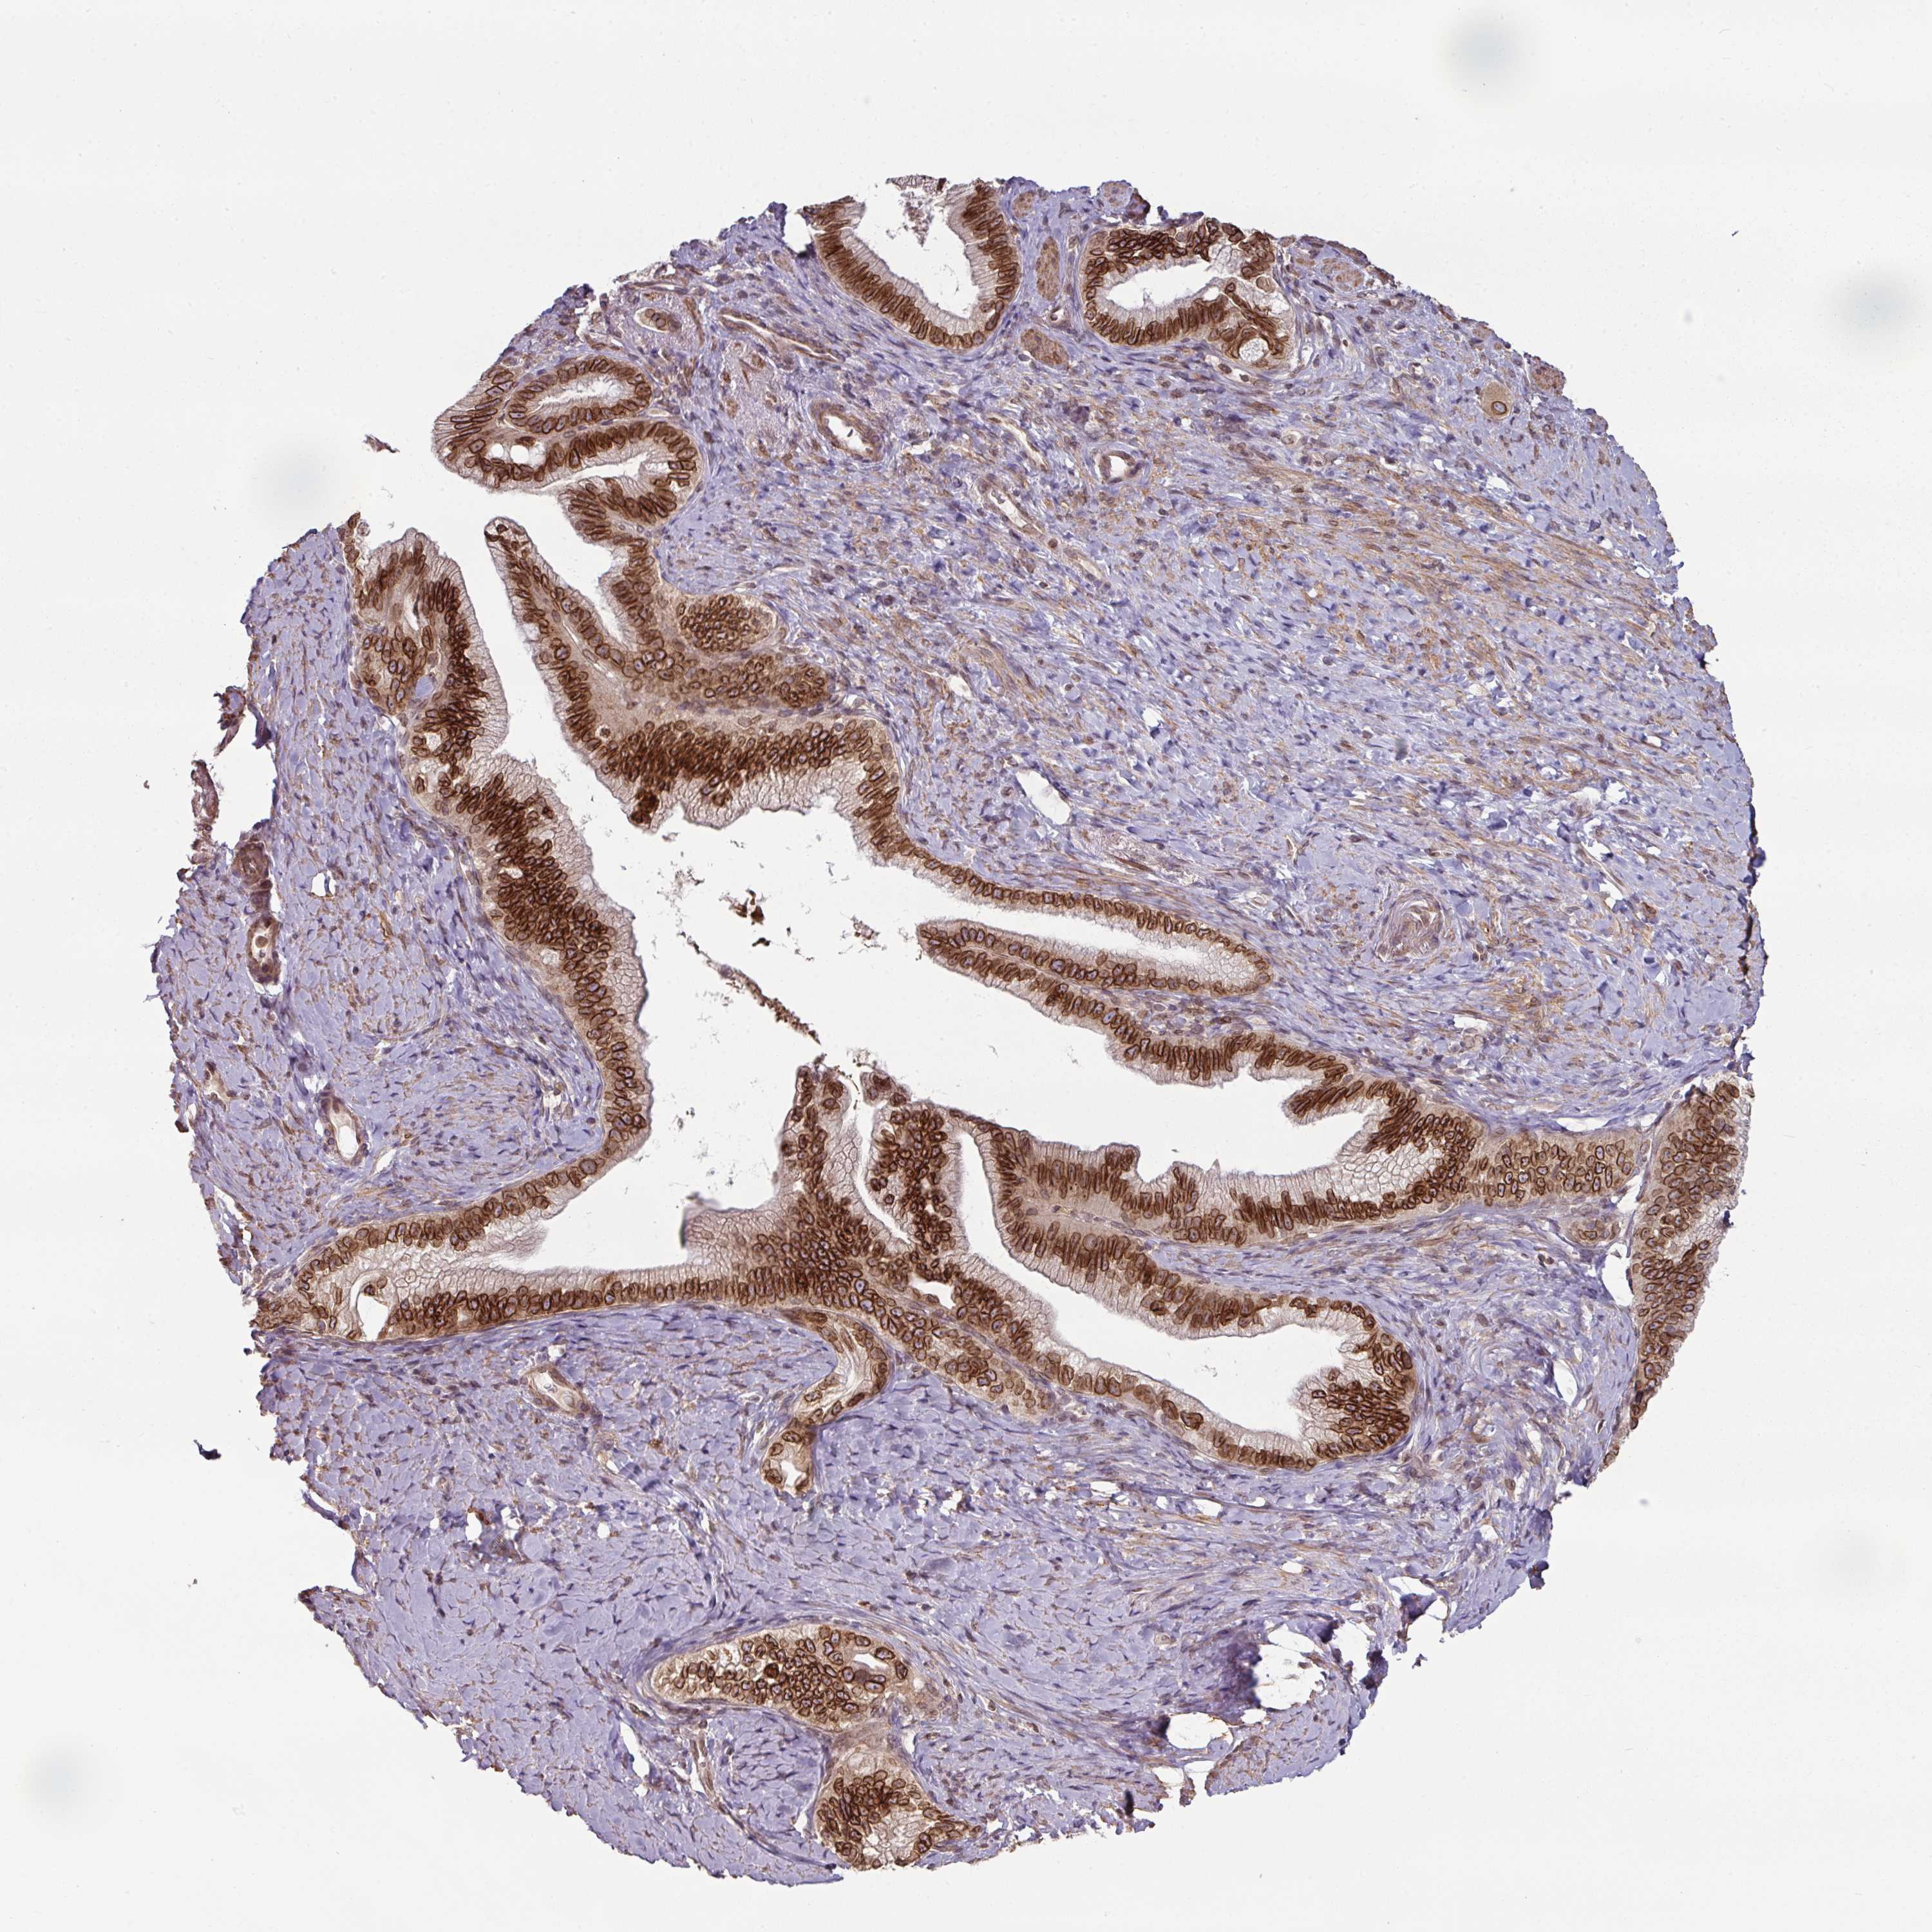

PANCREATIC CANCER - Protein expressioni

A mouse-over function shows sample information and annotation data. Click on an image to view it in a full screen mode. Samples can be filtered based on level of antibody staining by selecting one or several of the following categories: high, medium, low and not detected. The assay and annotation is described here.

Note that samples used for immunohistochemistry by the Human Protein Atlas do not correspond to samples in the TCGA dataset.

Antibody stainingi

Antibody staining in the annotated cell types in the current human tissue is reported as not detected, low, medium, or high, based on conventional immunohistochemistry profiling in selected tissues. This score is based on the combination of the staining intensity and fraction of stained cells.

Each image is clickable and will lead to virtual microscopy that enables deeper exploration of all samples and also displays staining intensity scores, fraction scores and subcellular localization as well as patient and tissue information for each sample.

Antibody HPA050110

Antibody CAB004293

Staining

High

Medium

Low

Not detected

Intensity

Strong

Moderate

Weak

Negative

Quantity

>75%

75%-25%

<25%

None

Location

Nuclear

Cytoplasmic/membranous

Cytoplasmic/membranous,nuclear

Adenocarcinoma, NOS

Adenocarcinoma, metastatic, NOS